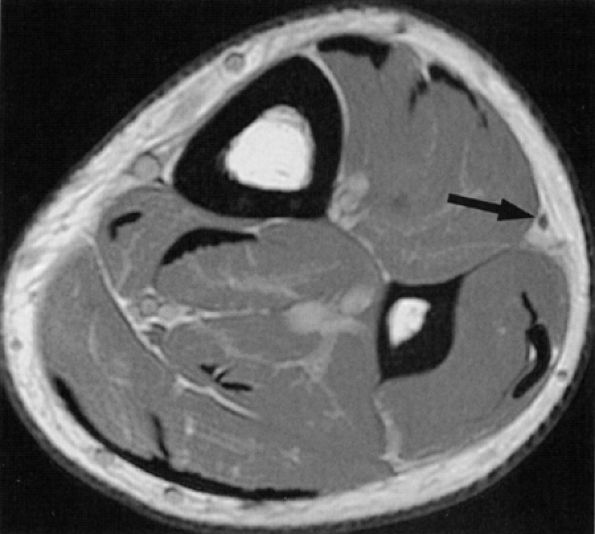

FIGURE 6.31 ● Surgically proven common peroneal neuropathy and denervation secondary to a hypertrophied biceps femoris muscle. (A) Axial T1-weighted image showing the common peroneal nerve (arrow) entrapped between a hypertrophied short head of the biceps femoris muscle (white asterisk) and the lateral head of the gastrocnemius muscle (black asterisk). (B) Axial T2-weighted fat-suppressed image displaying denervation edema in the anterolateral compartment muscles (arrows).